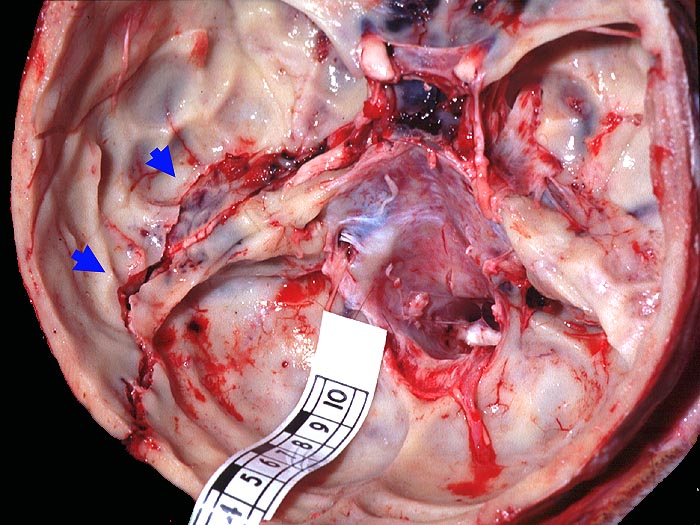

Schädelbasisfraktur

Frische Schädelbasisfraktur im Bereich der vorderen Schädelgrube entlang dem Os ethmoidale, im Bereich der Pars petrosa des Os temporale sowie bis in den Bereich der hinteren Schädelgrube entlang der Sutura lambdoidea links reichend.

Frische kortiko-subkortikale Hirnkontusionen. Blutige Otorrhoe links. Herdförmige diffuse frische Subduralblutungen (ohne raumfordernde Wirkung). Monokelhämatom.

Verkehrsunfall.